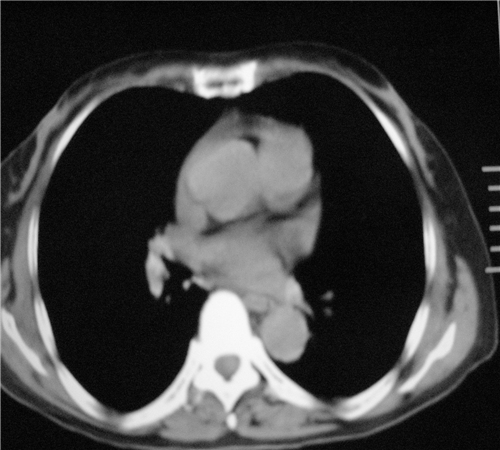

标题: CT26849:女67岁反复胸痛两天余,临床考虑夹层。 [打印本页]

标题: CT26849:女67岁反复胸痛两天余,临床考虑夹层。

右肺感染,未见夹层。

未见夹层

既然考虑夹层,建议强化!另:右下肺感染!

1)右肺感染性病变。2)建议行ct增强扫描或mri检查排除主动脉夹层。

双下肺感染,右侧显著。有无夹层,增强扫描后再诊断。

1. 感染性病变,2.未见夹层,3.食道未见异常。

平扫未见确切夹层征,建议必要时增强扫描或mri检查。